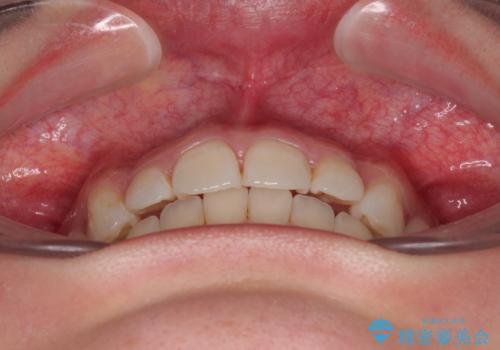

- 前歯のデコボコと突出感を気にして来院された患者様です。

極力目立たない装置を希望とのことで、インビザラインを用いて非抜歯で矯正治療を行うこととしました。

事前に親知らず2本を抜歯し、多少歯列を後方に移動できるように準備をした上で、なるべく歯と歯の間を削ることなくデコボコを解消できるように計画しました。

前歯の捻れを改善するとともに、口元が少しでも引っ込むように治療計画を立て、仕上げることができました。